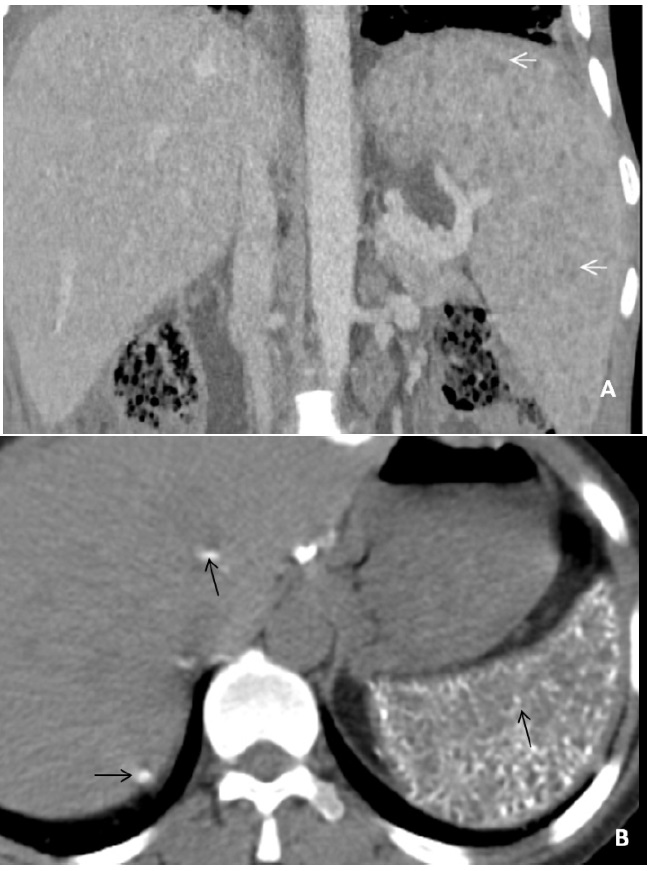

Hepatosplenic tuberculosis

Isolated hepatic or splenic involvement is rare in tubercular infection. It is almost every time associated with the lung or involvement of another abdominal organ. Mainly two broad types of features are there in hepatic or splenic tuberculosis, i.e. military or macronodular. The miliary type is associated with hematogenous dissemination, therefore involving the whole liver or spleen, resulting in liver/spleen enlargement and deranged liver functions. Whereas in macronodular type, dissemination is through a portal vein in which multiple hypodense lesions are observed scattered diffusely in the liver or spleen (Figure 7A). Calcification can also be seen in the chronic phase (Figure 7B). These macronodular presentations may confuse with abscess or metastasis. The involvement of the biliary tree by tuberculosis is even rarer, and its annual incidence is estimated to be 0.1%. If the biliary tree is involved, it is secondary to compression by hepatic granulomas. The gall bladder is rarely involved.

Figure 7: (A) A 40 years old male patient presented with pain abdomen and fever. The USG showed the presence of multiple hypoechoic lesions in the spleen, and a CECT abdomen was performed for further evaluation. The reformatted coronal image of the venous phase reveals hepatosplenomegaly and tubercular involvement of spleen in the form of innumerable tiny hypodense lesions diffusely scattered in splenic parenchyma (microabscesses) (white arrows). Liver biopsy was performed in the same patient due to persistent deranged liver function tests that demonstrated multiple caseating granulomas. Presently, the patient is on ATT and kept on follow-up every six weeks. (B) In another 60 year old male patient, who presented with cough and weight loss, non-contrast CT scan image in axial plane demonstrated calcified nodules involving splenic (black arrows) and hepatic parenchyma (white arrow) that signifies an old healed infection.

Adrenal tuberculosis

In about 10-30% of cases of Addison disease, adrenal tuberculosis is the most common infection found. The CT appearance of tubercular infection depends on its course and inflammatory process. CT findings of early tubercular infection in adrenal are typical bilateral adrenal enlargement with central necrosis (appears hypoattenuating on CT) with the peripheral enhancing rim (Figure 8A). In the late stages of the disease, the adrenal gland appears calcified and atrophic (Figure 8B).

Figure 8: A patient, 36 years old, presented with generalized weakness and significant weight loss in the recent past. On the CECT abdomen, there is an enlarged left adrenal gland showing heterogeneous enhancement with the central necrotic area (hallmark for active tubercular infection) (black arrow) versus normal right adrenal (white arrow). The patient kept on on ATT with four-drug therapy (Isoniazid, rifampin, ethambutol and pyrazinamide) for eight weeks (Intensive phase) followed by two drug therapy (Isoniazid and rifampin) for 18 weeks (Continuation phase). Another 45 years old male patient who had pulmonary tuberculosis in the past now presented with generalized weakness, continuous headache, hyper-pigmentation and vague pain abdomen from the last few years. He underwent a non-contrast computed tomography (NCCT) abdomen, which showed irregular bilateral adrenal enlargement with internal calcification (white arrows). Patient ‘B’ has restarted on ATT for the same.